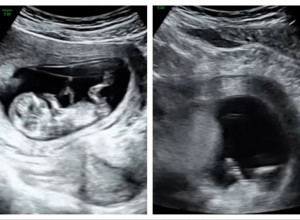

- Pregled je počeo uobičajeno, a onda je doktorka odjednom zinula u čudu dok je šokirano gledala u ekran. Uplašila sam se da nešto nije u redu, ali mi je objasnila da je sve u redu sa mojoj bebom dok je i dalje pokušavala da razazna nešto na ekranu. Moja beba je bila zdrava što je bilo i najvažnije. Pitala sam je zašto je tako gledala u ekran, a ona je u neverici odmahnula glavom i samo kazala da joj se nešto učinilo, ali da nemam razloga za brigu - kazala je Britani.

Zbunjena njenim ponašanjem fotografiju ultrazvuka bebe Britani je poslala u vajber grupu koju su činile najbliže žene njene porodice - mama, tetka, sestra. Pitala ih je da li vide nešto neobično na ultrazvuku bebe.

- Moja teka je prva uočila u gornjem desnom uglu nekakvu senu koja kao da je imala lice i ruku. Rekla mi je da je to božiji znak. Ona smatra da je to anđeo čuvar koji gleda i pazi na moju bebu što mi je bilo jako slatko. Sve do porođaja na svakom ultrazvuku ta sena je stajala na istom mestu - ispričala je Britani, a prenosi Dejli mejl (Daily mail).